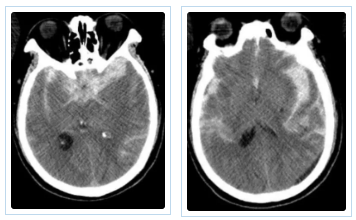

近日,面对一位古稀老人颅内破裂的“不定时炸弹”——复杂脑动脉瘤,我院神经外科团队成功应用全球前沿的自膨式动脉瘤瘤内栓塞器(WEB) ,完成了我院首例该技术下的动脉瘤精准介入治疗。 紧急救治 古稀老人突发“颅内炸弹” 71岁的张先生(化名)突发剧烈头痛伴右侧肢体乏力,经120紧急送入我院。急诊迅速启动卒中绿色通道,经头部CT及CTA检查,诊断为“广泛蛛网膜下腔出血、左侧大脑中动脉分叉部动脉瘤”。此类动脉瘤破裂风险极高,如同颅内的“不定时炸弹”,治疗刻不容缓。 术前颅脑CT见广泛蛛网膜下腔出血 CTA见左侧大脑中动脉分叉部宽颈动脉瘤 创新破局 全球新技解难题 神经外科介入团队立即组织多学科讨论,详细研判病情,制定了开颅夹闭与微创介入栓塞两套方案,家属明确选择微创手术方案。面对位于复杂分叉处且瘤颈宽大的动脉瘤,团队决定应用全球前沿的自膨式动脉瘤瘤内栓塞系统(WEB)进行治疗。在神经外科、介入中心与麻醉科的通力协作下,成功将自膨式动脉瘤瘤内栓塞系统(WEB)装置植入动脉瘤腔内,完成栓塞治疗,历经2小时。术后,造影显示动脉瘤完全隔绝,载瘤动脉通畅良好,危机解除。 技术优势 瘤内扰流新选择 自膨式动脉瘤瘤内栓塞系统(WEB)装置形似精密编织的迷你网篮,专为分叉部宽颈动脉瘤设计。相较于传统支架辅助栓塞,自膨式动脉瘤瘤内栓塞系统(WEB)技术体现了神经介入领域的重要创新: 操作简化: 单一器械即可完成治疗,流程更简洁。 安全性提升: 避免支架植入,降低了血栓等并发症风险。 患者受益: 术后无需长期服用抗血小板药物,减轻了身心及经济负担。 此例自膨式动脉瘤瘤内栓塞系统(WEB)植入术的成功开展,标志着我院在复杂脑动脉瘤微创治疗领域取得新突破,为患者提供了高效的治疗选择。作为国家卫健委能力建设和继续教育神经外科建设中心,贵州航天医院神经外科将持续依托优质资源,深化对外协作,以技术创新护航百姓健康。 神经外科专家简介 廖洪民 神经外科党支部书记、主任,主任医师 临床擅长:从事神经外科临床工作30年,对颅脑损伤、脑肿瘤、脑血管病等具有丰富诊疗经验,擅长救治重症颅脑创伤、脑出血微创治疗、脑肿瘤显微手术治疗、脑立体定向手术等。 中国医师协会神经外科分会专科认证医师、贵州省医学会神经外科分会青年委员、遵义市医学会神经外科分会常务委员、遵义市中西医结合学会脑心同治专业委员会常务委员、中国生命关怀协会脑卒中救治及康复照护专业委员会委员、贵州省脑损伤评价质控中心专家库成员、遵义市脑损伤评价医疗质量控制中心专家。 朱家伟 神经外科副主任医师 临床擅长:从事神经外科工作26年,擅长颅脑损伤救治及脑出血微创手术。 遵义市医学会神经外科分会委员、遵义市中西医结合学会脑心同治专业委员会常务委员。 黄建军 神经外科副主任医师 临床擅长:从事神经外科工作20年,对神经外科常见病、急危重症有丰富诊疗经验,熟练掌握神经外科微创手术。 神经外科科室简介 基本情况 贵州航天医院神经外科于2008年独立建科,是首批国家卫健委能力建设和继续教育神经外科建设中心,贵州省神经外科介入联盟单位。现有专业技术人员17人,其中高级职称4人,中级5人,初级7人。 科室配备STORZ神经内镜系统、德国莱卡手术显微镜,国产西山开颅动力系统、蛇牌双极电凝、Mayfield头架等颅脑手术设备,以及无创和有创颅内压监护仪、正中神经刺激仪、脑循环康复治疗仪、排痰机、下肢康复训练器、气垫床、多参数监护仪等现代化医疗设备,为病区各种急、危、重患者的观察、监护和治疗保驾护航。 专科特色 (一)脑出血微创手术治疗 应用范围:各种病因导致的自发性脑出血(高血压脑出血、脑淀粉样血管病相关脑出血、抗凝药物相关脑出血等)。 技术优势:微创、精准、恢复快。 (二)颅脑病变显微切除术 应用范围:颅内各种占位性病变(脑囊肿、脑肿瘤等)。 技术优势:精确度高、创伤小、恢复快。 (三)颅脑创伤综合救治 应用范围:各种类型的颅脑损伤、创伤性颅内血肿及颅脑创伤并发症、后遗症等。 技术优势:快速精准诊断、个体化手术与监护、早期康复干预,伤者病死率低、并发症少。